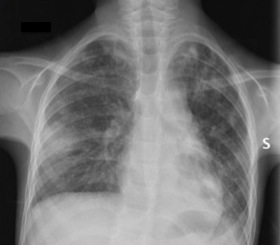

All’ecografia dell’addome: ispessimento di ultima ansa ileale, cieco, colon ascendente; vengono pertanto programmati esami endoscopici per sospetta malattia infiammatoria cronica intestinale. Per febbre, durante la degenza, esegue Rx torace: infiltrati interstizio-alveolari bilaterali (Figura 2).

Sierologie per polmonite e aspergillo negative. Esegue Quantiferon: positivo! Per tale riscontro effettua 3 aspirati gastrici: test per i bacilli acido-alcol resistenti (BAAR) positivo, e PCR (Polymerase Chain Reaction) positiva per Mycobacterium tuberculosis.